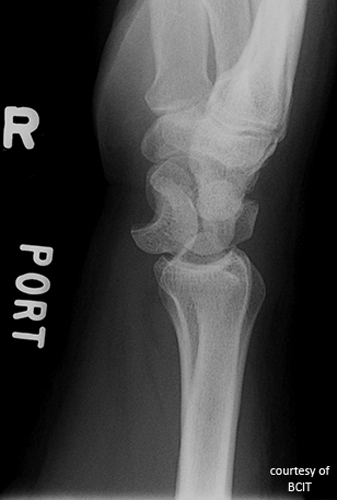

What injury is indicated by a visible fat pad (sail sign) on elbow X-ray?

Occult elbow joint fracture causing joint effusion.

What causes most posterior elbow dislocations, and what bone is often fractured?

FOOSH on an extended elbow; often involves coronoid process fracture.

What is the most common elbow fracture in adults?

Radial head fracture.

Why is the 'fat pad sign' important in elbow trauma?

It indicates joint effusion, often due to an occult intra-articular fracture even when the fracture line is not visible.